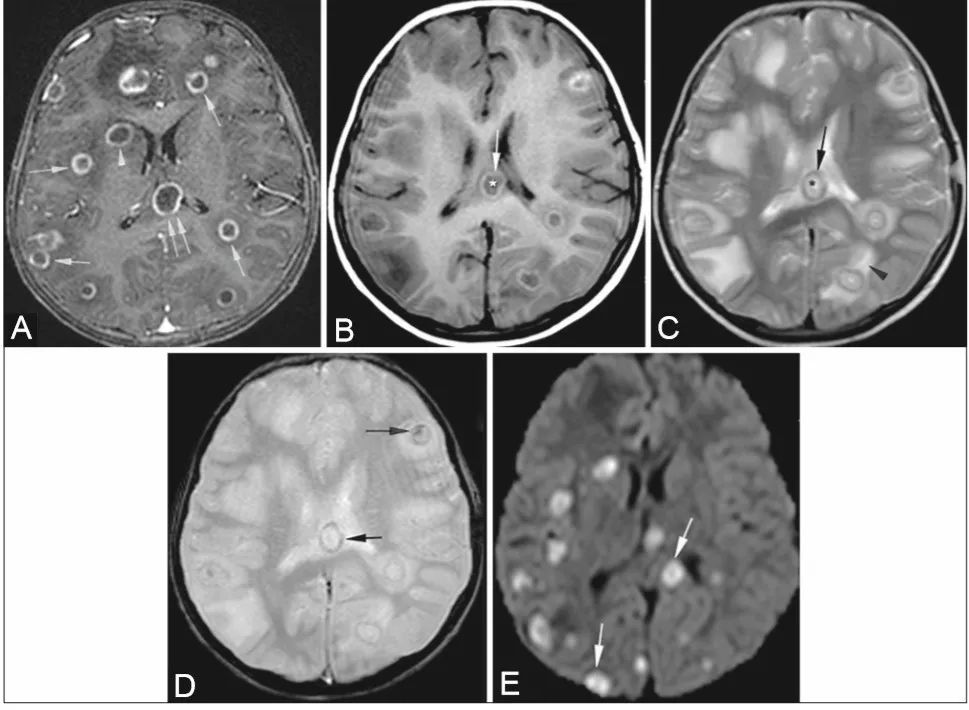

女性11岁,急性髓系白血病,以头痛为主要表现。

增强后T1W像(A):大脑半球多发环形强化病灶(单箭),胼胝体(双箭),右侧基底节(箭头)。T1W图像(B): 核心低信号 (*),高信号环(箭)。T2W图像(C):核心高信号(*),低信号环(箭),周围水肿(箭头)。GRE图像(D):病灶壁和核心出血灶(箭)。DWI (E)显示肉芽肿弥散受限(箭头)。组织病理学:多发性曲霉菌丝和中央坏死。

免疫功能受损的患者患真菌感染的风险增加。在真菌病原菌中,念珠菌和曲霉菌是引起脑脓肿的主要病原菌。呼吸系统是通过吸入孢子而感染的主要部位。在曲霉菌属中,烟曲霉最常见。它可以通过血源途径从肺部进入中枢神经系统,也可以直接从副鼻窦和鼻腔进入。少数情况下由于外伤或外科手术引起。免疫功能受损患者出现头痛、嗜睡、偏瘫和癫痫等非特异性症状,应当怀疑脑曲霉菌病。曲霉菌的一个显著特征是其血管侵袭性,经常导致早期脑梗死,伴有或不伴有出血。

常见的感染部位包括胼胝体、基底神经节、丘脑和脑干,以及灰白质交界区。常见有以下三种方式:(1)皮质下边界不清的病灶T2呈高信号,T1呈低信号。(2)多发环形脓肿[如本例患者]。(3)靠近主要感染源(如副鼻窦)的硬脑膜异常增强。脓肿在T1W上呈低信号,周围或中央有高信号区,与出血相对应。在T2W上,它们表现为核心高信号,边缘呈低信号。这种低信号环是由真菌凝结形成的,其中含有大量的铁、锰和镁,这些物质存在于真菌菌丝的外围。约25%的病变发生出血,在梯度回波T2W上可以看到晕染区域。